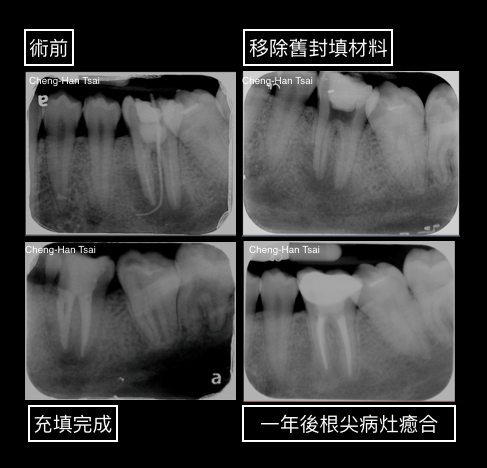

然而,有些已經做過根管治療的牙齒,還是有根尖病灶未癒合或疼痛不舒服的狀況,這些情況甚至在初次的根管治療完成數個月到數年後發生,如此一來,您需要專科醫師的評估,甚至需要根管重新治療。

一般來說,根管的重新治療的成功率會比初次治療下降許多(初次治療85-90%、重新治療65-80%);因此,我們建議若是需要根管再次治療的患者,在初診時接受根管治療(牙髓病學)專科醫師的診療評估,並安排最適合您的療程,才能節省寶貴的時間,並確保您能了解並選擇最好的治療。